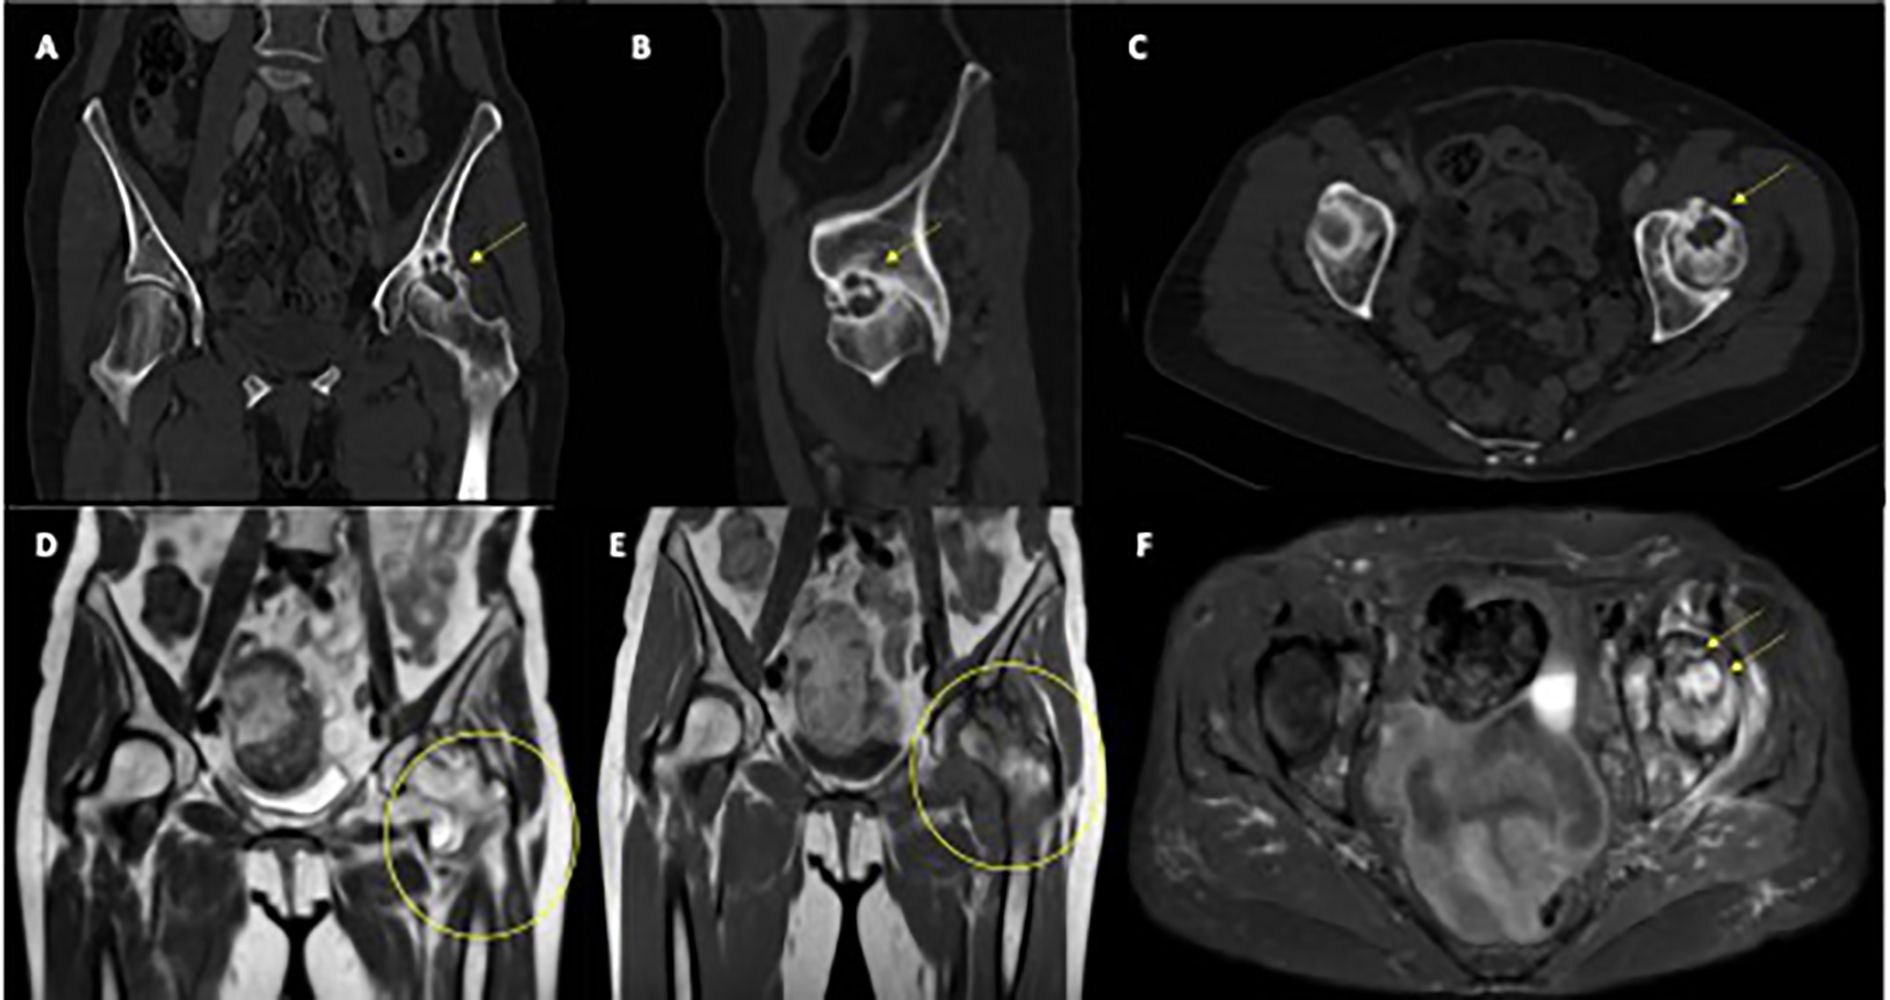

First restaging scans demonstrated complete radiologic regression of both the gastric and pancreatic lesions. Incidentally, imaging also revealed severe left coxarthrosis characterized by joint space narrowing, coarse geodes, and femoral head deformation (Figures 1A–C).

Figure 1. Radiological features of left femoral head osteitis during immunotherapy. (A–C) CT scans show progressive deformation and sclerosis of the left femoral head (yellow arrows). (D, E) Coronal T1-weighted MRI images demonstrate diffuse bone marrow edema and joint effusion (yellow circles). (F) Axial T2-weighted MRI highlights extensive marrow edema and synovial hypertrophy (yellow arrows).

Pelvic and spinal imaging revealed marked progression of left hip arthropathy, raising suspicion for an osteonecrotic process (Figures 1D–F). MRI of the left hip showed features consistent with osteonecrosis, including diffuse bone marrow edema, focal osteochondral lesions of the acetabular roof, abundant joint effusion, synovial hypertrophy, and adjacent muscle edema (Figures 1D–F).